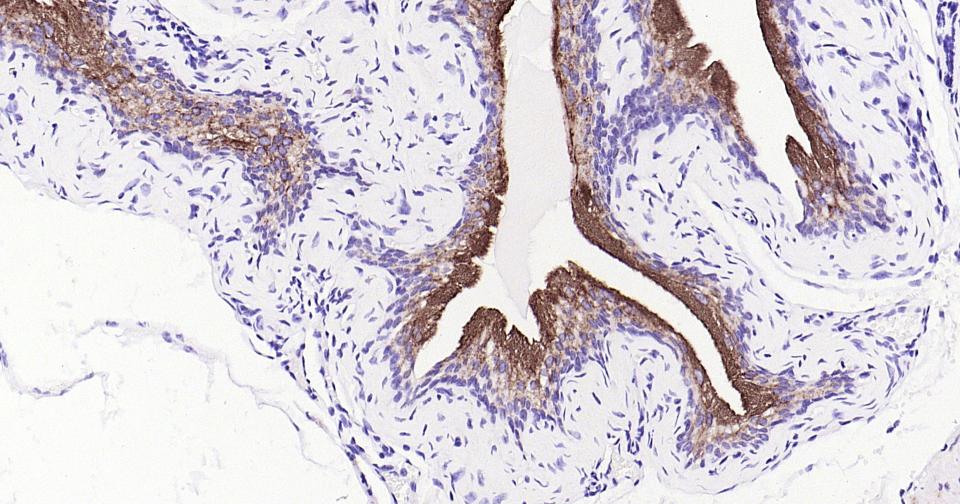

The asymmetric unit membrane (AUM) forms numerous plaques, which cover the apical surface of the urothelium. These plaques are thought to strengthen the urothelium and reduce the risk of rupturing during ladder distention. They are composed of four major integral membrane proteins called uroplakins (UP). The uroplakin family comprises UPIa, UPIb, UPII, and UPIII. Family members are conserved among several species, including human, mouse, rat, rabbit, dog, pig and sheep. UPIa and UPIb form tightly packed structures with UPII and UPIII, respectively. This pairing is required for normal urothelial plaque formation and is regulated by proteolytic processing of the uroplakin proteins. Uroplakins are expressed in normal urothelium and are used as specific markers of urothelial differentiation. They are also expressed in a majority of transitional cell carcinomas of the bladder (TCCs), which make the uroplakins a useful marker for detecting bladder cancer metastasis and for staging and monitoring chemotherapeutic response.

IHC-PHuman, Mouse1:100-500

交叉反应: Human, Mouse